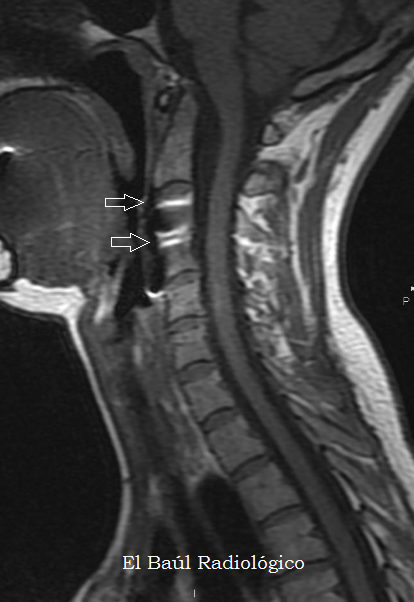

La mayoría de estos objetos están fabricados en titanio, material no ferromagnético, que no supone ningún peligro para las personas que se van a someter a una exploración de Tomografía por Resonancia Magnética (TRM). Sí, en cambio, provocan la aparición de artefactos por susceptibilidad magnética que impiden la correcta evaluación de la zona quirúrgica, lo cual supone un inconveniente. Cuando el material utilizado es de acero, los artefactos que aparecen son mayores. En este caso no hay que temer por las posible consecuencias porque es imposible que los tornillos de la artrodesis, correctamente insertados, sean removidos por la fuerza del campo magnético del imán. Otro efecto indeseable es el calentamiento del metal que se puede producir, cuando se realizan exploraciones muy largas. Hay que tenerlo en cuenta y ser resolutivos. Con dos o tres secuencias es suficiente para realizar un examen de TRM cervical.

(Most surgical devices in use today are made from titanium, non-ferromagnetic material, which poses no danger to people who are about to undergo a MRI exam. They provoke the appearance of magnetic susceptibility artifacts that prevent us the proper evaluation of the surgical site. When the material used is steel, the artifacts are greater. In this case it is impossible that arthrodesis screws are removed by the magnetic field strength of the magnet. Another effect indeseable is heating the metal, when scans are very long. This should be taken into account. With two or three sequences is enough to made an examination of TRM).

FIGURA 4) Secuencia FSE-T1. La placa metálica de titanio produce artefactos de susceptibilidad magnética (flechas) que impiden la correcta visualización de los cuerpos vertebrales en los que está insertada, pero no dificultan la exploración de la médula y el canal espinal.

(FSE-T1 MRI Sequence. The titanium metal plate produces magnetic susceptibility artifacts (arrows) that prevent the correct visualization of the vertebral bodies in which it is inserted, but does not difficult the exploration of the cord and the spinal canal).

FIGURA 5) Secuencia FSE-T2. La placa metálica de titanio produce artefactos mayores  que en las imágenes FSE-T1 (flechas).

(FSE-T2 MRI Sequence. The titanium metal plate produces, black and white, magnetic susceptibility artifacts (arrows).